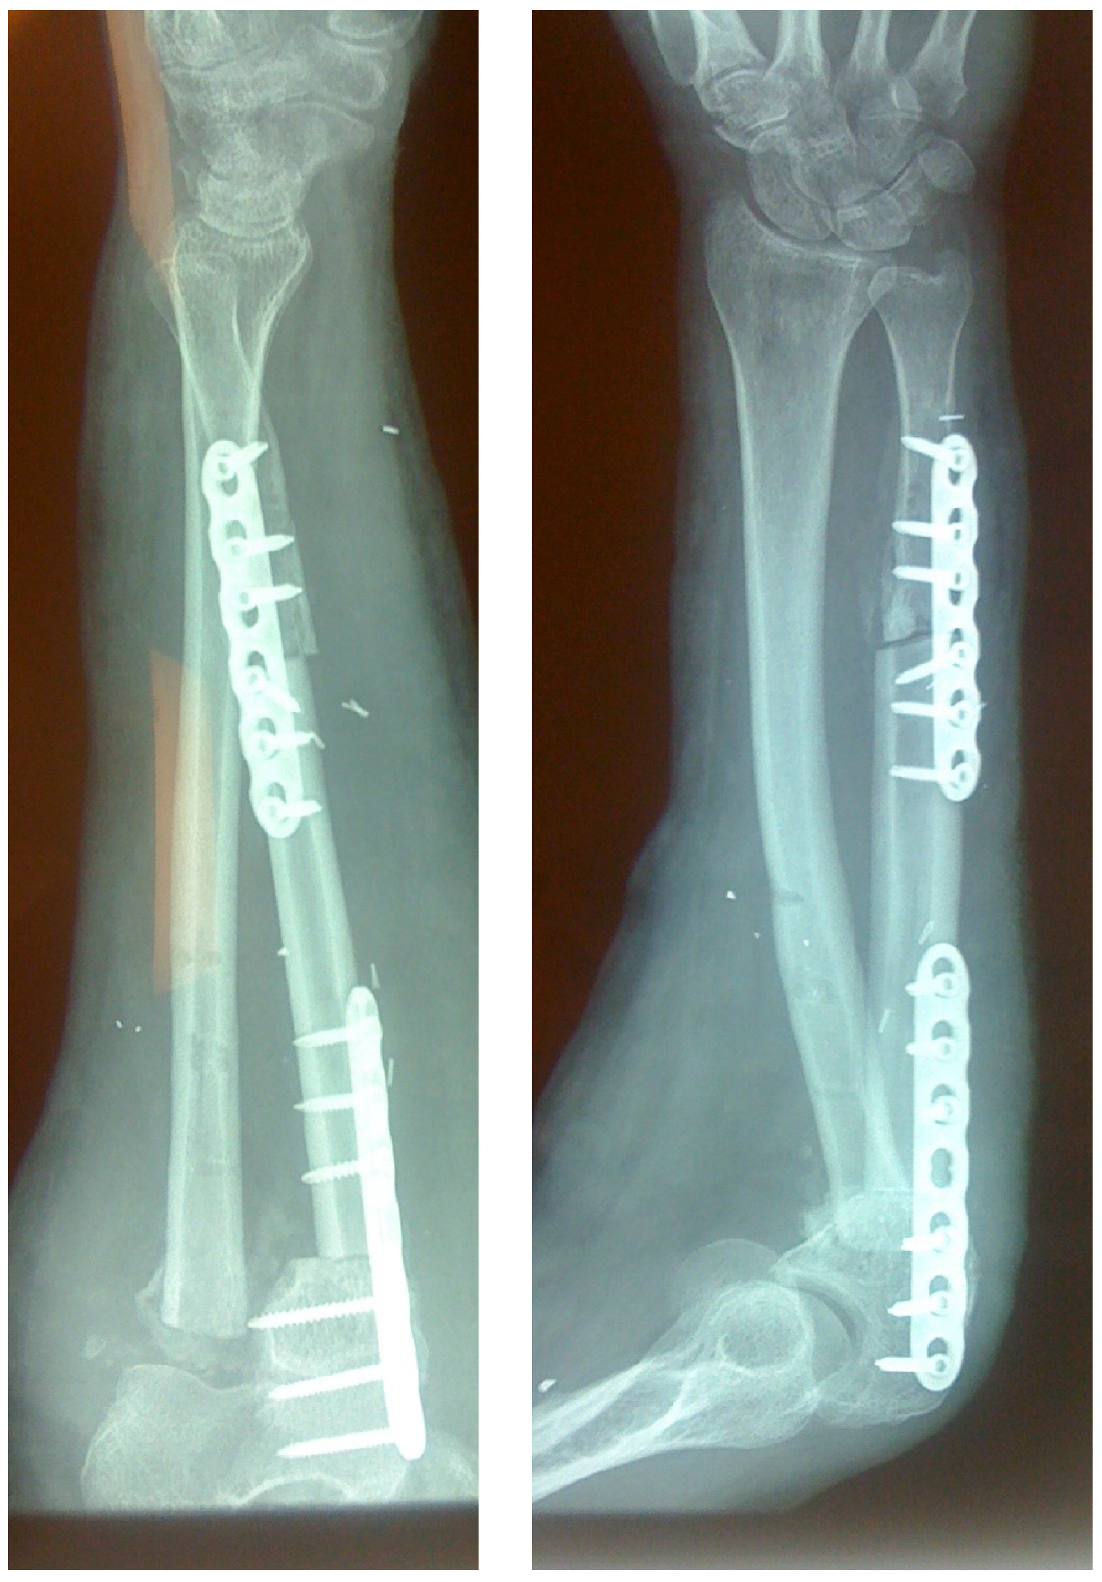

In cases of bone fracture non-union, the surgeon excised scar tissue along with the sequestrum until reaching bleeding bone, following the removal of previously inserted metalwork. For tumor excision cases, the surgeon resected the bone tumor with clear margins or the entire compartment in cases of tumor-induced bone cortex breakage (Figure 1). At this stage, the length of the bone defect was measured to determine the appropriate length of the fibular graft to be harvested (Figure 2). The fibular graft fixation was accomplished using dynamic compression plates (DCPs) or anatomical plates, with a minimum of six cortices engaged on each side using either simple or locking screws (Figure 3). Once the osteosynthesis is completed, it is time to proceed with the vessel anastomosis. First, the peroneal vein is anastomosed to the radial or ulnar vein using 8-0 nylon monofilament sutures. Following this, the surgeon performs the arterial anastomosis using the same type of suture as previously. Simple interrupted stitches are preferred over a continuous suture technique and the anastomosis could be either end to end or end to side using a microscope.

Figure 1. (AE): A giant cell tumor of the distal radius that invades the distal articular surface, distal radioulnar joint, and palmar cortex of the radius. The selected treatment involves excision of the distal radius, including the pronator quadratus muscle, the proximal carpal row, and the distal third of the ulna. (F,G): Wrist arthrodesis using an intercalated free pedicled vascularized fibular graft was the treatment of choice.

Figure 2. (A,B): Measuring the skeletal defect is essential to harvest the appropriate length of the fibular graft.

Figure 3. Large ulnar skeletal defect treated with FVFG, fixated using two LC-DCP plates.